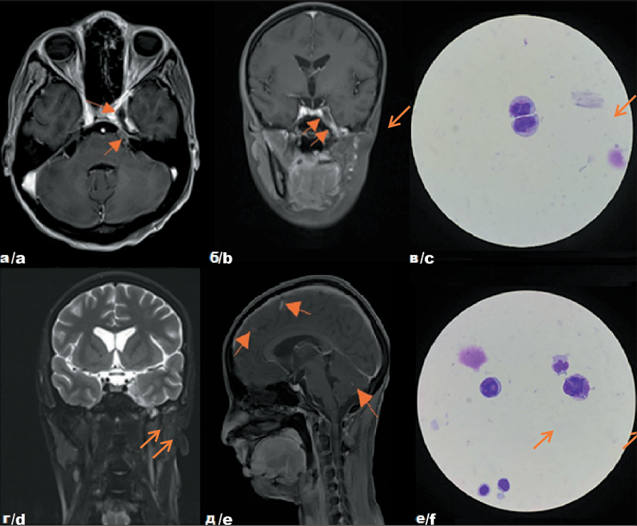

5. Рис. 5. Собственные результаты исследований пациентки Т. с диагнозом: Эмбриональная рабдомиосаркома параменингеальной локализации с интракраниальным распространением, стадия Т2bN0M0 IRSIII. Рецидив I, до начала противорецидивного лечения – на томограммах в аксиальной (а), фронтальной (б) проекциях и после комбинированного лечения – на томограммах во фронтальной (г) и сагиттальной (д) проекциях, цитологическая картина (в) (е) спинномозговой жидкости. Примечание: рисунок выполнен авторами